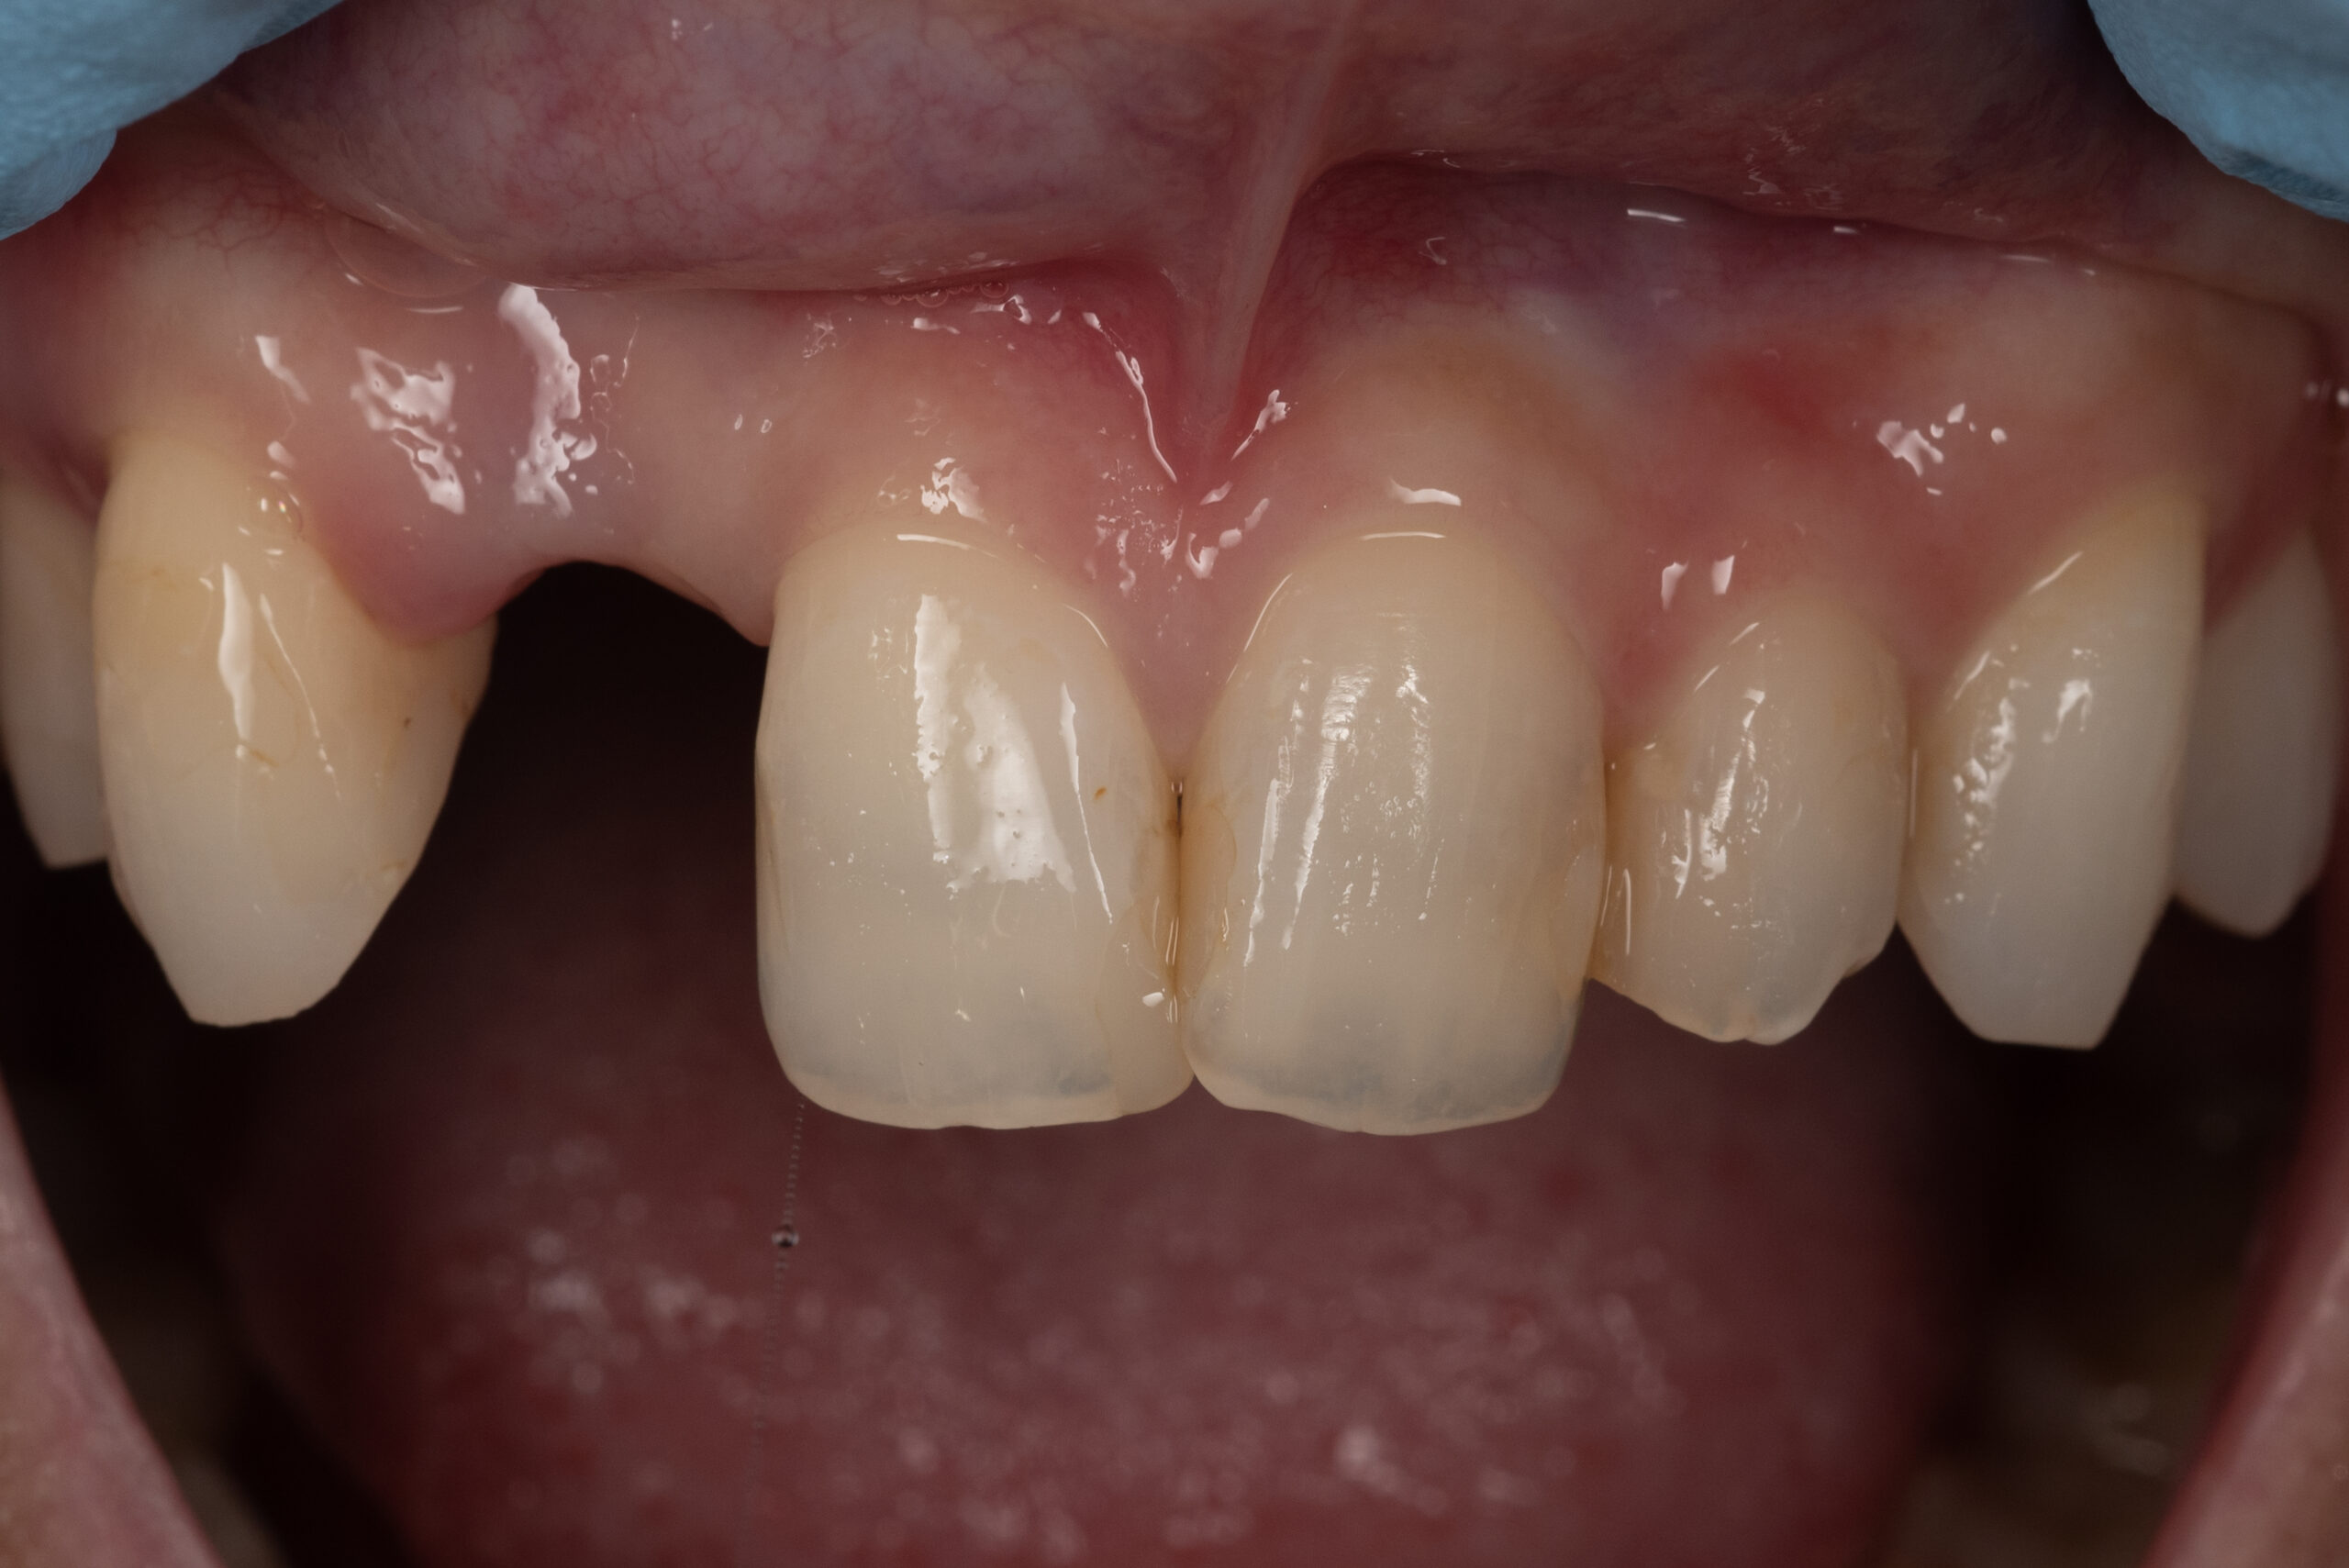

症例

歯周病による歯ぐきの後退を

改善した症例

結合組織移植術(CTG)+根面被覆術

主訴

「歯ぐきが下がって見た目が気になる」「冷たいものがしみる」

下顎前歯の歯ぐきの後退が気になると来院された患者様の症例です。

診査・診断

- 下顎左側中切歯に歯肉退縮と根面露出を認める

- 歯周病が進行し、歯ぐきのボリュームが減少

- 見た目の違和感と知覚過敏の症状がある状態

1枚目:術前

2枚目:術後

3枚目:初診時の状態

4枚目:歯周基本治療終了時の状態

5枚目:手術中(CTG実施時)

6枚目:術後の状態(回復後の歯肉ライン)

◆ 術後の変化

- 歯ぐきの厚みと高さが改善

- 根面が覆われ、見た目も自然に

- 知覚過敏も軽減し、快適に

- 患者様にも大変ご満足いただきました